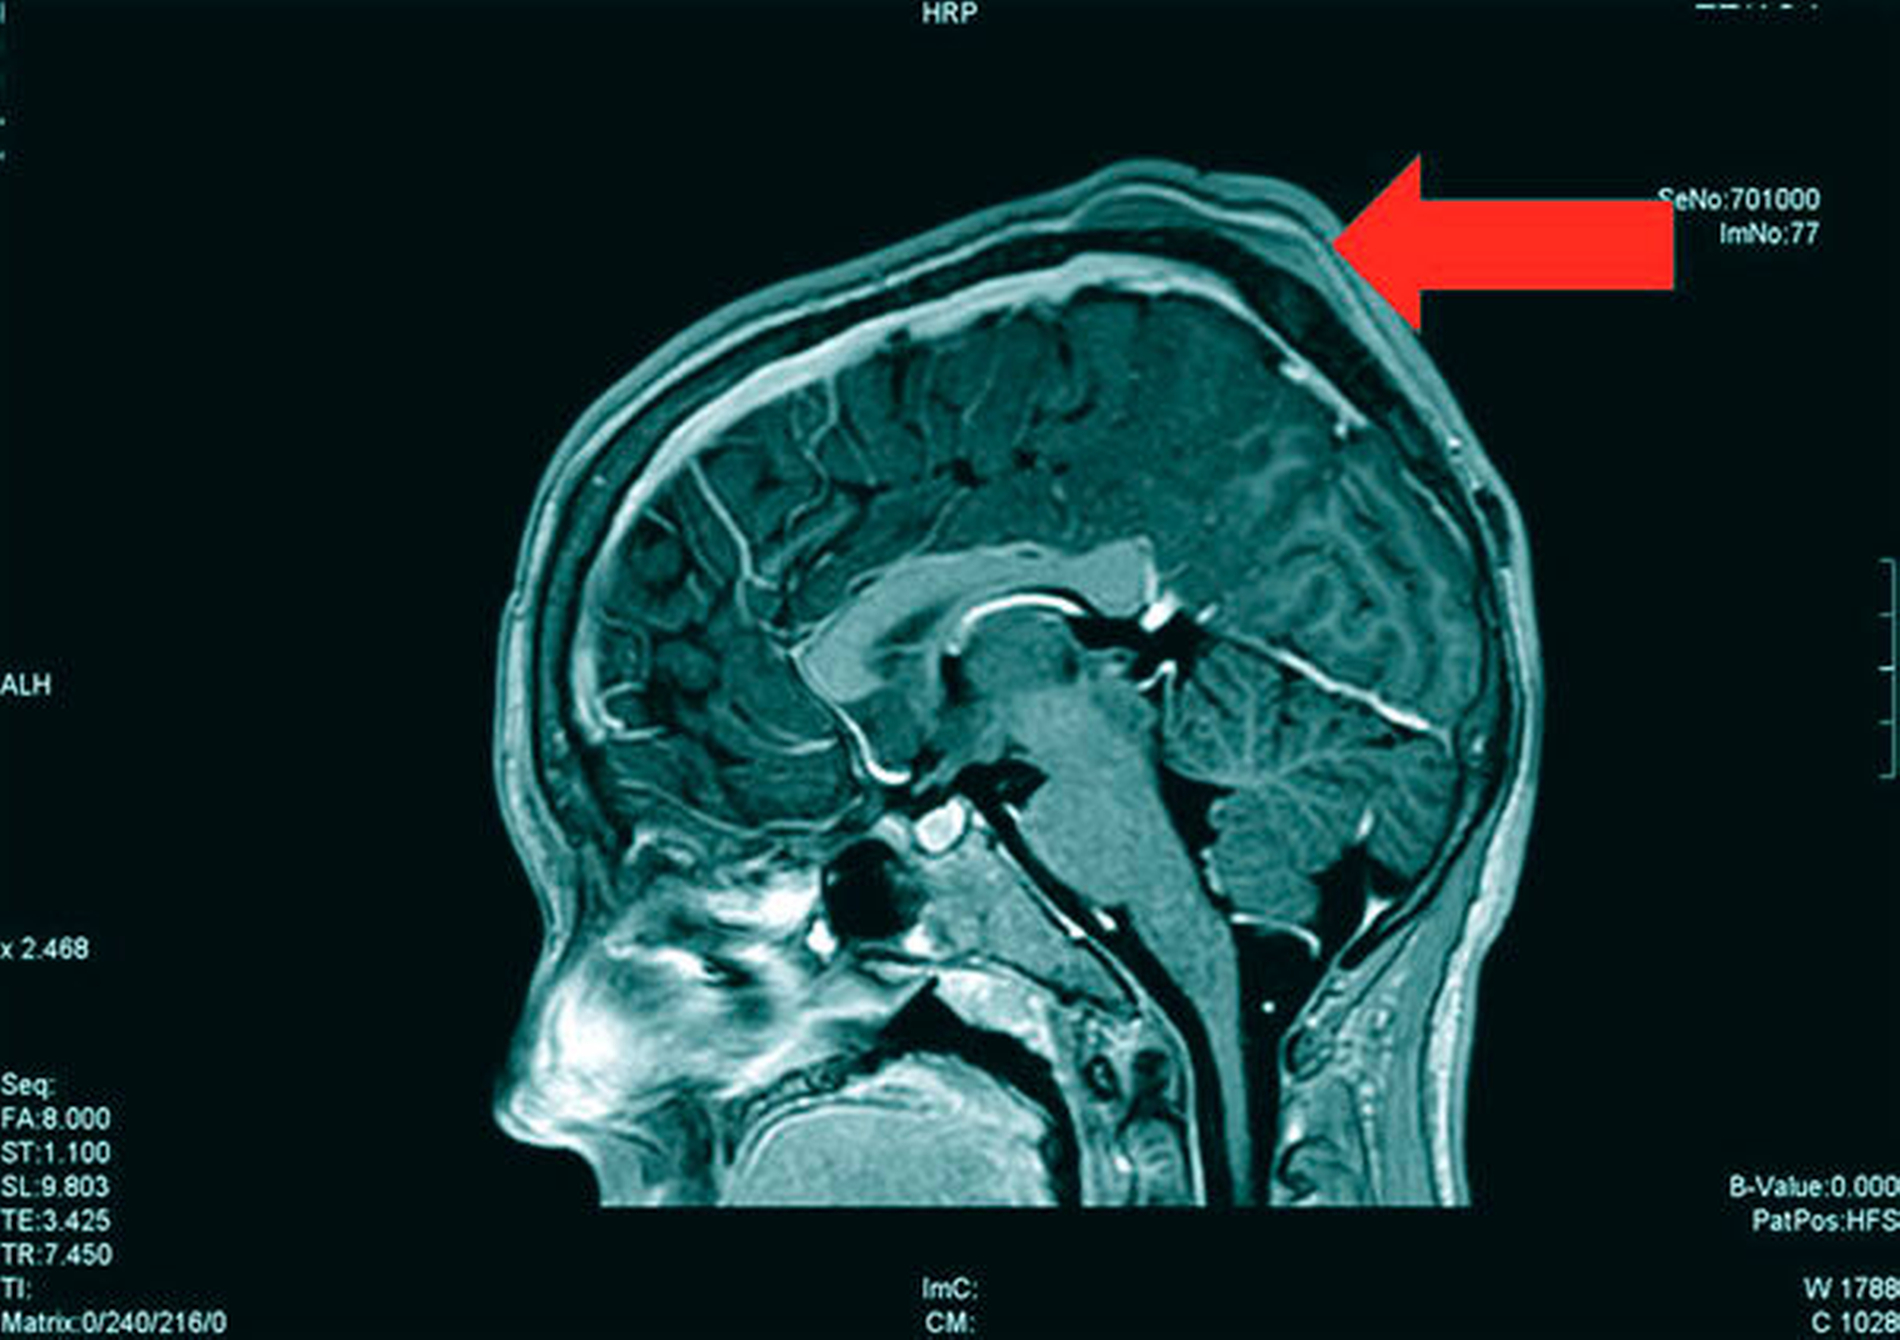

Die Magnetresonanztomografie des Neuro- und des Viszerokraniums erbrachte den Nachweis eines Areals erhöhter Kontrastmittelaufnahme im Bereich des basalen Kieferwinkelrandes links mit einer Ausdehnung von 3,1 cm x 2,3 cm. Im Bereich der behaarten Kopfhaut zeigten sich subkutan T1-hypointense, zum Teil polylobulierte Läsionen mit Verdacht auf epidermale Zysten sowie subgaleale T2-hypointense, flächig kontrastmittelaufnehmende Läsionen mit Verdacht auf Osteome (Abbildungen 3a bis 3d).